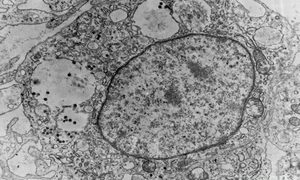

トリ白血病ウイルス(ALV)はレトロウイルスで、世界中のニワトリに数種類の良性・悪性新生物(腫瘍)を発生させる原因となります。ALVには7つの異なる亜群(subgroups)(A~J)がありますが、J亜群は群れの間で発生する最も重要な原因と...